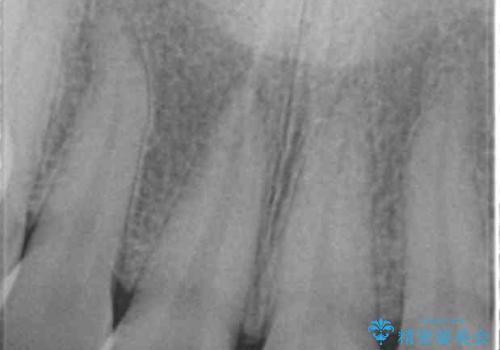

- 歯ぐきに、にきびのようなものができ治らない、と治療を希望され来院されました。

歯髄の検査、X線検査より神経の失活が確認されたので、根管治療・ファイバーコア築盛 ・ジルコニアクラウンの製作、と治療を進めます。